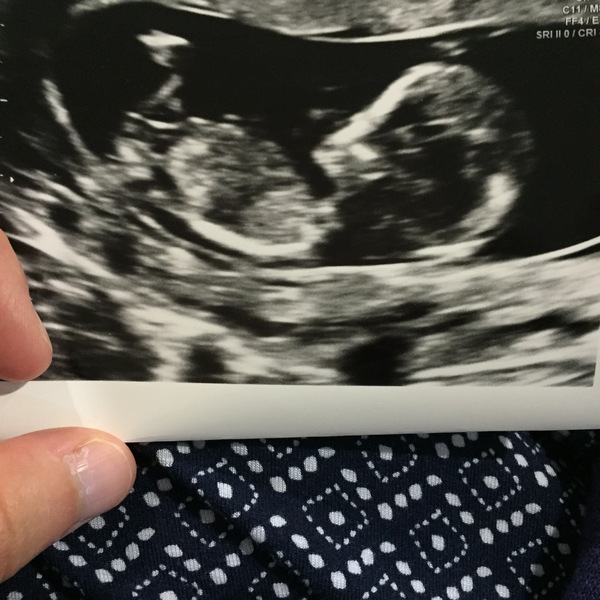

Phew! Everything looks ok. I might have had a little cry. Baby was mostly asleep but did see him/her jumping after I went for a wee.

Potato mine is 7cm and at the top of my uterus, not blocking the exit. Hopefully it will behave.

elle congratulations on the lovely scan! Grin I had a few tears at mine yesterday. It was more the look of complete elation on OHs face and the relief when I realised baby was still doing well as the screen wasn't facing me but he could see everything.

Elle lovely scan Grin

7cm is big but not too bad. I recommend making sure you have a store of ice packs, cocodamol and paracetamol at home just in case you get the dreaded red degeneration. You probably have a fairly low risk but it doesn't hurt to be prepared.